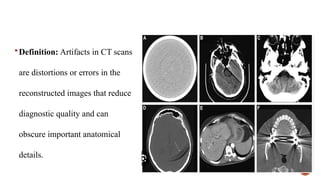

 Definition: Artifacts in CT scans

are distortions or errors in the

reconstructed images that reduce

diagnostic quality and can

obscure important anatomical

details.